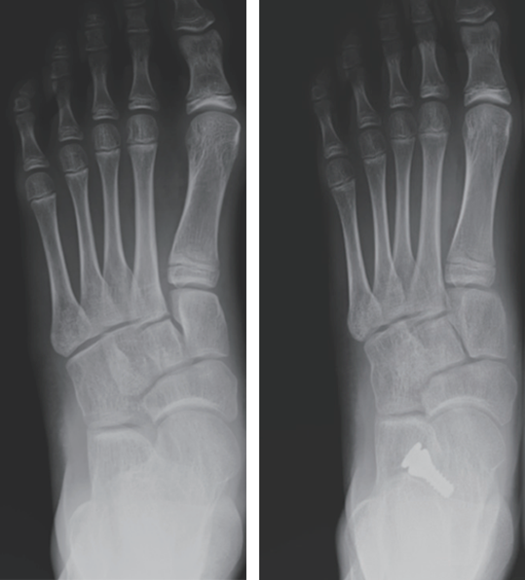

图12:Hyprocure距下关节制动器矫正青少年柔软性平足(正位X光片,右侧为术后)

图13:侧位X光片,下方为术后。